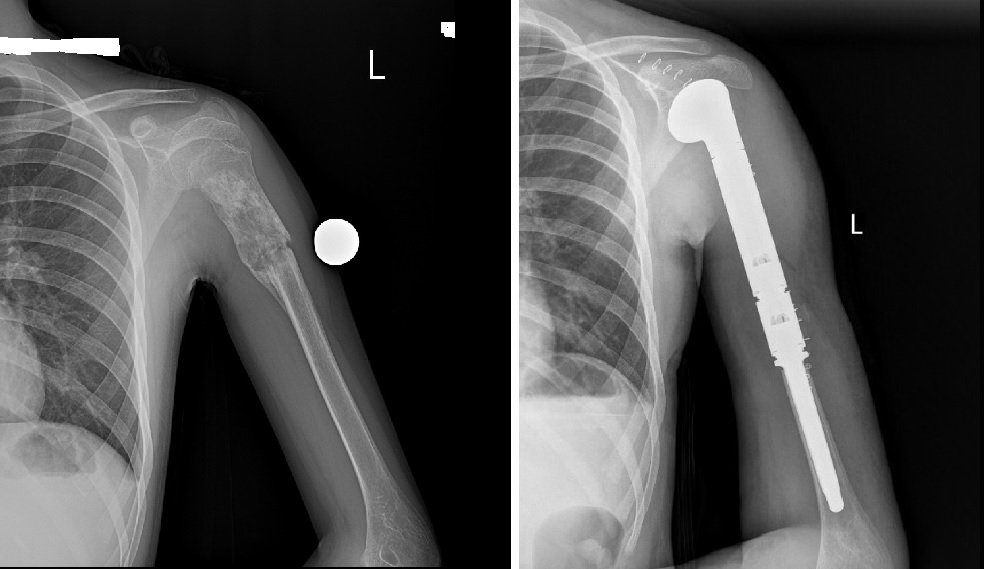

Улсын Нэгдүгээр Төв Эмнэлэг/УНТЭ/-ийн Үений мэс заслын баг болох ХҮСҮСТ-ийн дарга М.Отгонбаяраар ахлуулсан баг Монгол Улсад анх удаа атгаал ясны дээд 2/3-г хамарсан том хэмжээний ясны хортой (osteosarcoma) хавдрын тохиолдолд хавдрыг бүхэлд нь аван мега-протез суулгах мэс заслыг амжилттай хийж гүйцэтгэлээ.

Ясны хавдрын үед том хэмжээний имплант суулгах мэс заслыг анх 2015 оноос эхлэн доод мөчдөд хийж эхэлсэн ба энэ удаагийнх нь дээд мөчид хийсэн анхны тохиолдол юм.

Тус эмчилгээний тохиолдлын мега-протез нь тухайн хүн өсөж томроход сунгагдах боломжтой тул дахин солих шаардлагагүй юм.